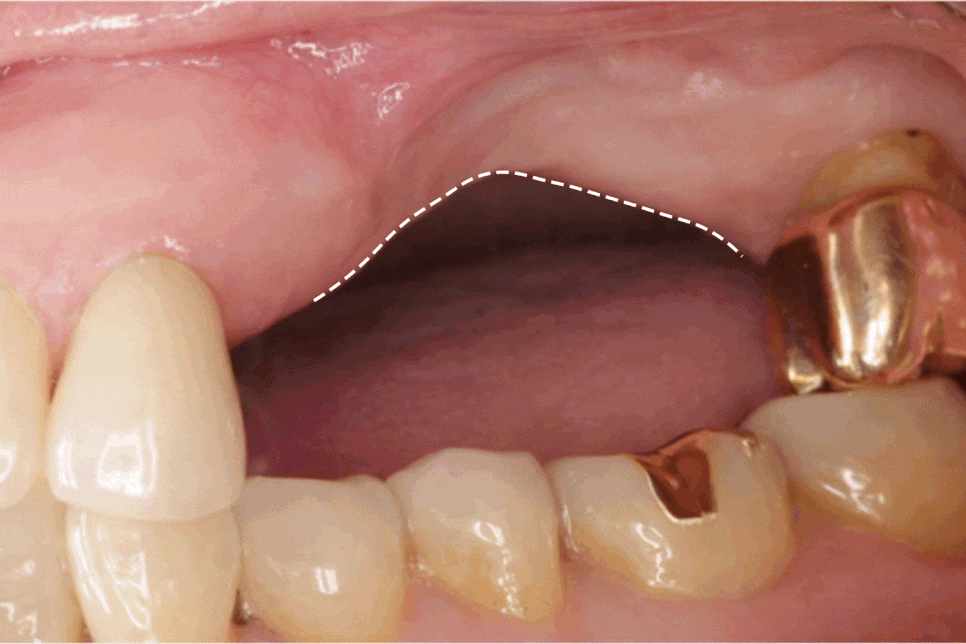

<치조골 흡수>

치아가 존재해야 치조골에

지속적이 자극이 전달되는데

치아가 상실되면 이러한 자극이 사라지면서

해당 부위의 치조골이 점차 줄어듭니다.

시간이 흐를수록 치조골의 양이 감소하면

이후 임플란트를 진행할 때

뼈이식과 같은 추가 처치가 필요할 수 있습니다.

<임플란트>

치아가 빠진 부위의 치조골에

픽스처(인공 치근)을 식립한 후

그 위에 보철을 연결하는 방법으로,

자연치와 유사한 기능을 회복할 수 있으며

인접치를 삭제하지 않고

치료할 수 있다는 장점을 가집니다.

또한 저작 기능 회복과 함께

치조골 흡수를 줄이는 데에도 도움을 줍니다.